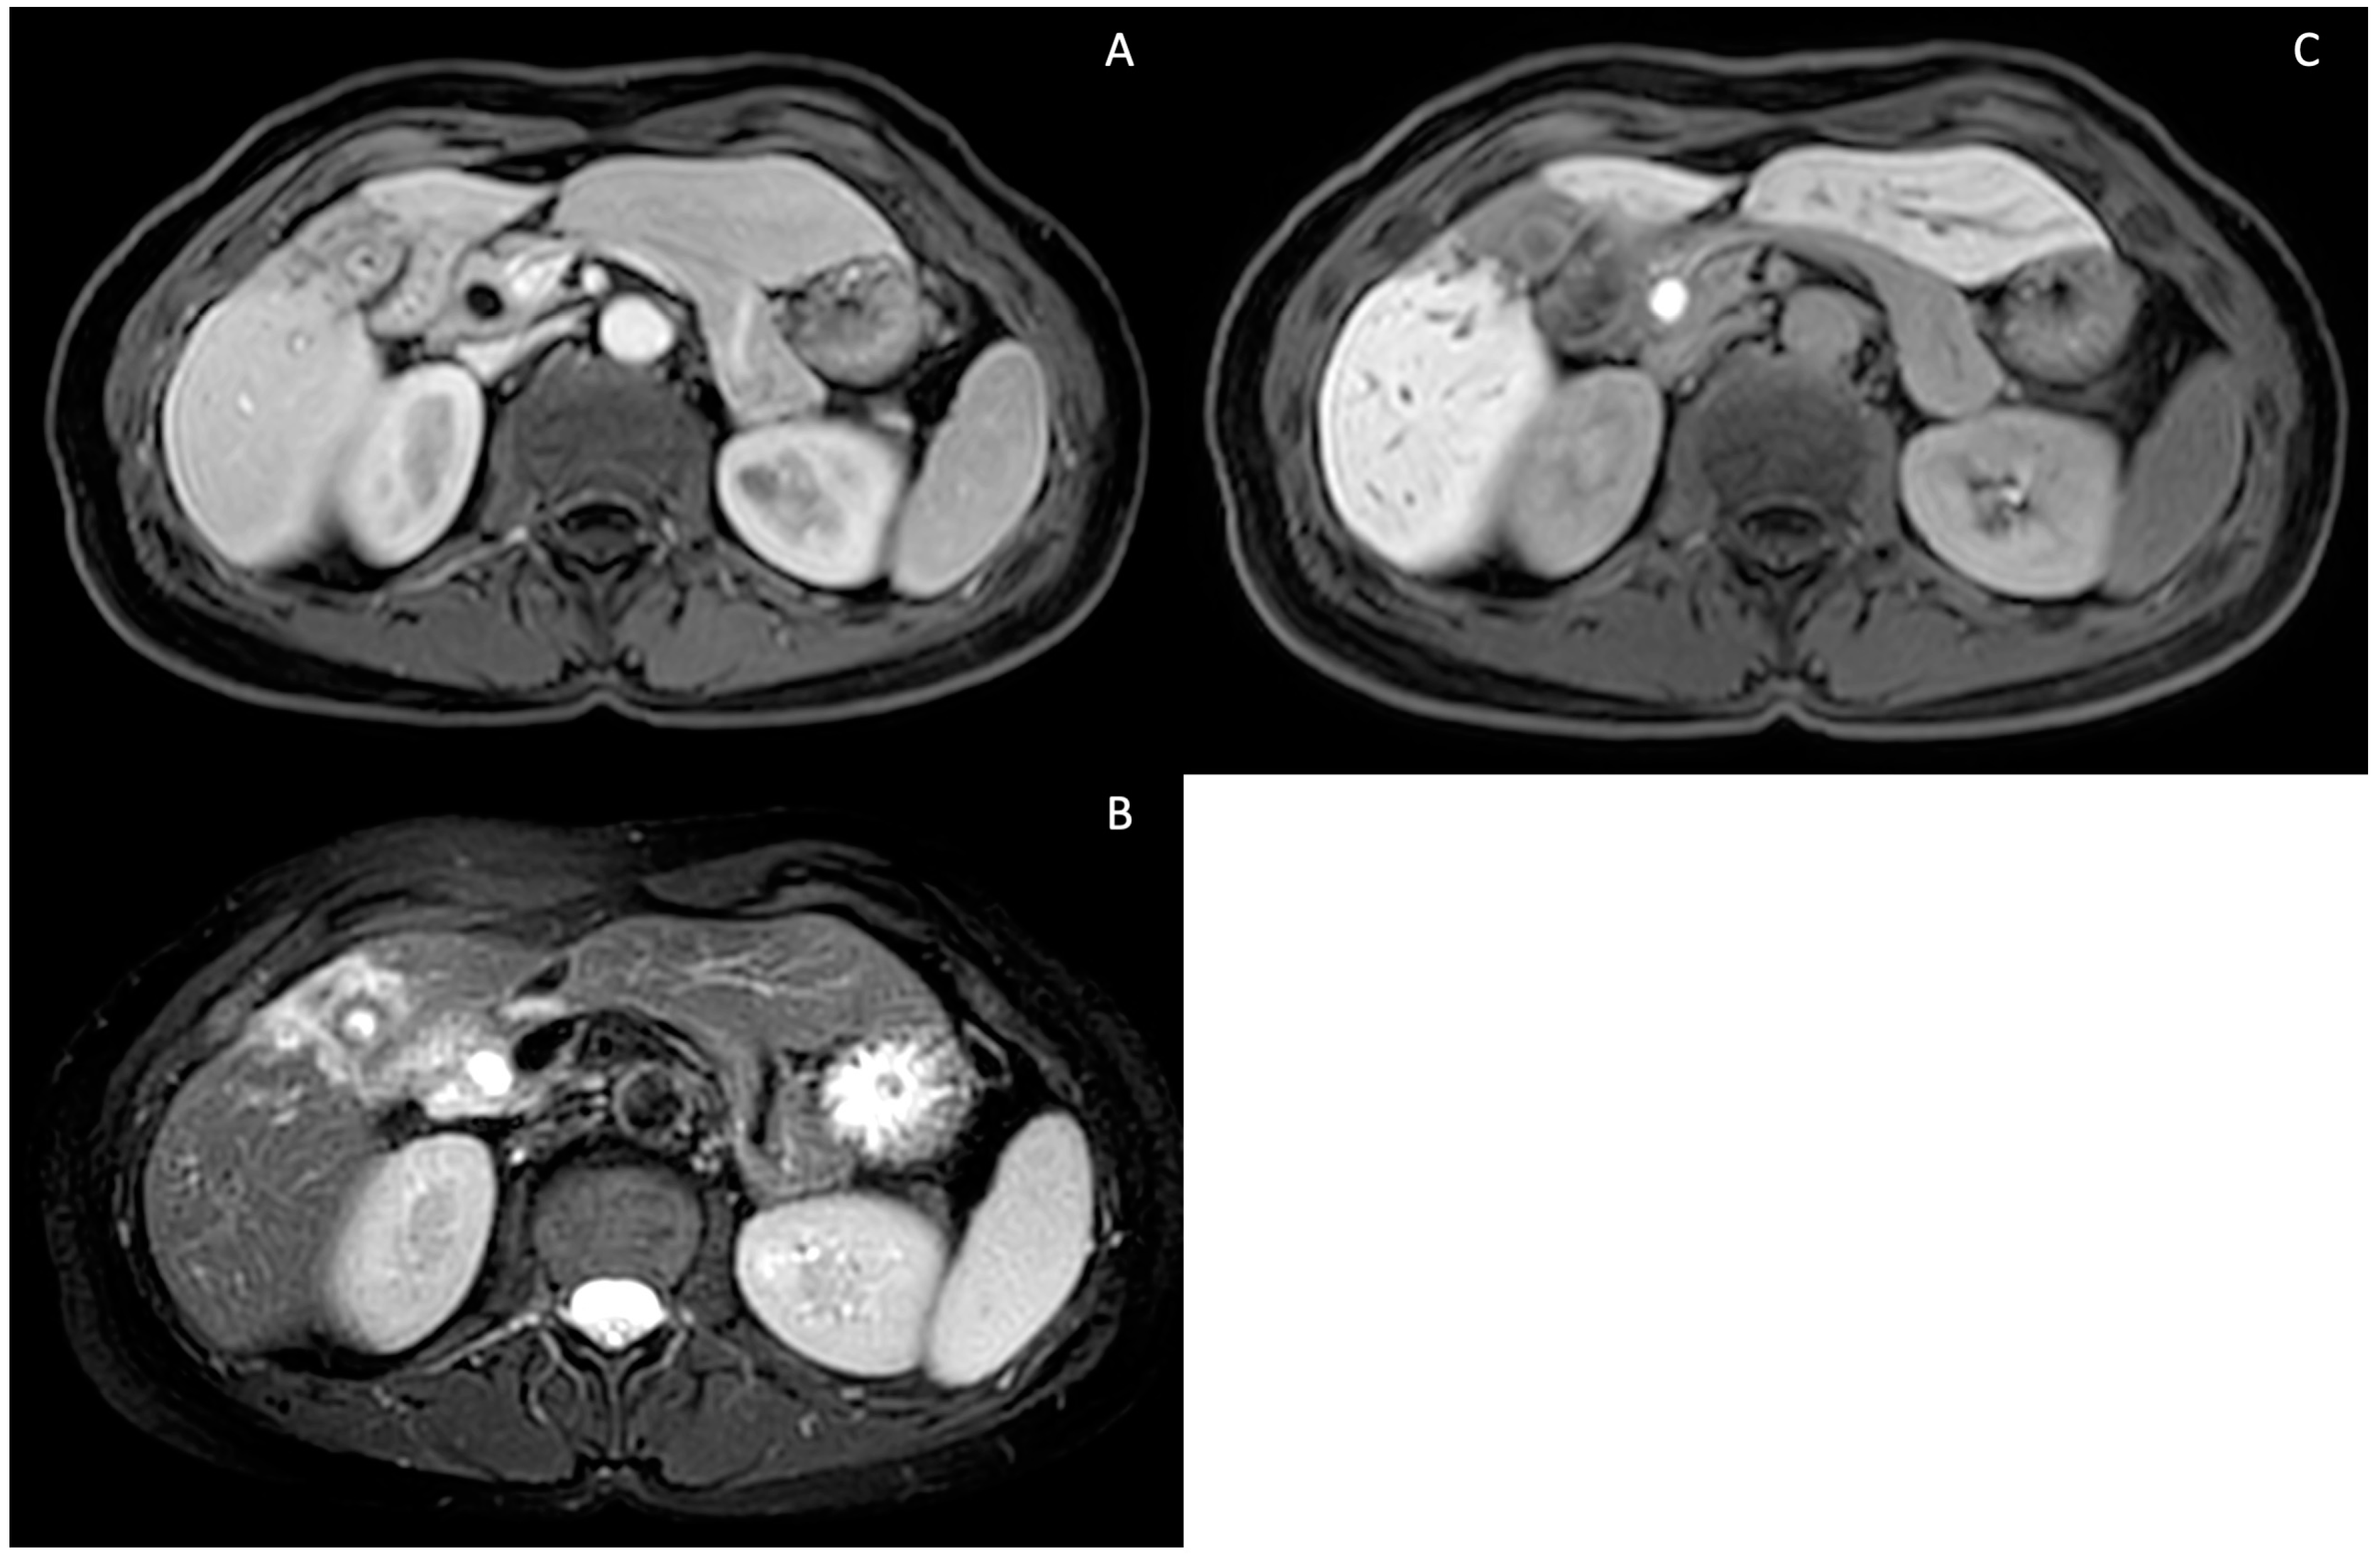

5. Technical Aspects of MRI in PSC

6. Cholangiographic and Liver Parenchymal Changes in PSC